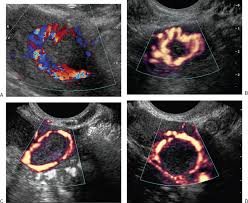

Advanced colour Doppler for Implantation Rate improvement

Advanced colour doppler is a sonography method to study blood supply of various organs in our body. In the context of infertility, the method used is transvaginal sonography and objective is to study blood supply to organs of reproductive such as, endometrium, uterus and corpus luteum. If the blood supply is not adequate, measures should be taken to correct it. Chances of embryo implantation (henceforth referred to only as implantation) can be increased by 30% if the blood supply to these organs is brought to correct level.

As mentioned above, we use this technique to monitor flow to various reproductive organs. First let’s talk about blood supply to endometrium. Poor blood supply results in poor oxygen level. This causes implantation failure. There are 4 zones in endometrium which are studied for blood supply for implantation. With the help of colour doppler doctors can monitor to what level the supply has reached. Endometrium showing vascularity in zone 3 & 4 signifies good levels, implying high chances of embryo implantation to be successful. Second let’s talk about blood flow to corpus luteum, which is formed to support hormones required for implantation. This is important information as doctors can give supplements of hormones required for improving implantation.